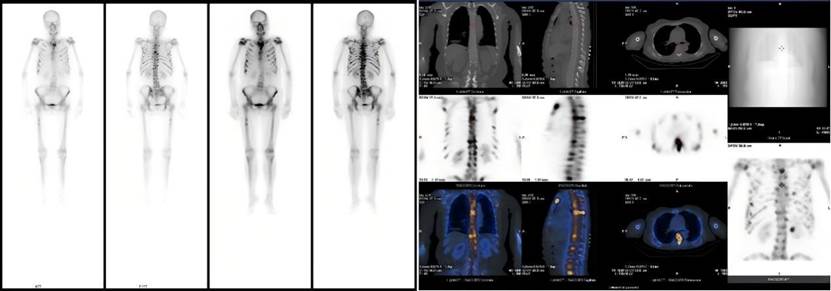

患者因不明原因发热、剧烈骨痛伴体重骤降前来就诊。入院后,全腹及胸部CT未见明显异常,但血常规提示白细胞、淋巴细胞、血小板及红细胞计数均显著降低。为进一步探明病因,临床医生安排了全身骨扫描(SPECT/CT),结果显示全身多处骨骼放射性浓聚,初步怀疑为肿瘤骨转移,其诊疗方向指向实体肿瘤,但其CT却未见明显病灶,诊断陷入了困境。临床医生随即安排可以全身扫描尤其对肿瘤病变尤为敏感的PET-CT检查。

△患者全身骨扫描(SPECT/CT)核医学显像图

经PET-CT检查,患者全身骨弥漫性明显代谢增高,其他脏器均并未找到明确的实体原发灶,这样的显像结果推翻了肿瘤骨转移的初步诊断。核医学科医生看到这样的显像结果,并结合患者的临床表现,一个新的诊断方向在脑海中回荡:淋巴瘤?血液系统疾病?按照这一方向,为患者进一步进行了骨髓穿刺等检查,终于这个凶手被找到——急性淋巴细胞白血病